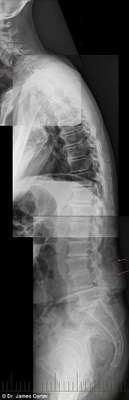

As imagens de raio-x abaixo mostram os malefícios do uso excessivo de smartphones e tablets para o corpo de adolescentes e crianças. Espinhas dorsais completamente curvadas que resultam em problemas graves de coluna e para o pescoço é a principal consequência da tecnologia para a saúde da nova geração.

17 anos, 16 anos e 7 anos

17 anos, 16 anos e 7 anos - Dr. James Carter

A condição, chamada de ‘text neck’ (‘Pescoço de mensagem’, em português), é observada em pessoas que sentam com suas cabeças a frente do corpo para interagirem com os seus smartphones ou tablets durante algumas horas.

Em geral, o peso da cabeça humana varia entre 4,5 kg e 55, kg, e a projeção do pescoço para frente faz com que o peso seja mais difícil de suportar, o que aumenta a probabilidade do surgimento de dores musculares e o encurvamento da espinha dorsal.